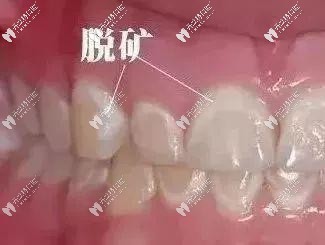

牙齒脫礦現(xiàn)象

牙齒脫礦也叫脫鈣,指人的牙齒牙釉質(zhì)表面的鈣磷脫落,致使牙齒色澤改變,成白色或微黃的斑點(diǎn),影響美觀,更嚴(yán)峻的,牙釉質(zhì)脫落,牙齒上有明顯的淺凹陷或細(xì)溝。